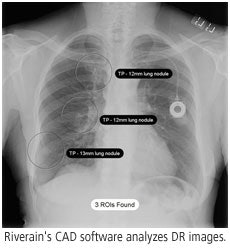

Riverain of Miamisburg, OH, will demonstrate continued improvements in the algorithm for the company's RapidScreen Digital software, and will also talk up the improving reimbursement situation for computer-aided detection (CAD) lung studies with digital radiography.

Since the 2005 RSNA show, Riverain has made improvements in RapidScreen's CAD algorithm that boost the software's sensitivity and specificity. The number of false positives produced by the software has also declined, down to three per study.